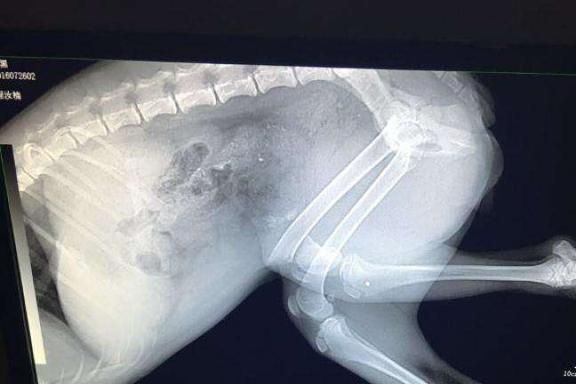

影像检查有超声检查、CT、核磁共振、X光,但是许多铲屎官并不清楚这些检查之间有什么区别,就让兽医小明来一一说明。

如果狗狗患了外伤,譬如伤到骨头等部位,那么X光是最优先的选择,因为它出片的速度很快,但是它的缺点是没办法细致观察狗狗的情况,如果想要进一步观察的话,那么就可以选择CT检查。

如果是胸部方面的疾病,X光拍片能够粗略检查狗狗的心脏、、主动脉、肺等,但是要想结构更加清晰的话,那么胸部CT还是更好的选择,它的准确性会高于常规的X光,但是CT检查的辐射剂量会明显高于X光。